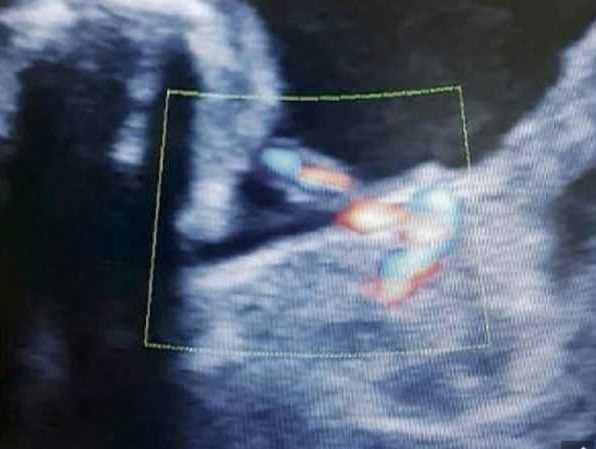

Tiếp tục sử dụng phương pháp siêu âm 4D, bác sĩ bất ngờ phát hiện ra bụng thai nhi không hề có nước hay dịch mà là một bào thai khác phát triển không hoàn chỉnh. Bào thai này có chân tay nhưng không có tim và cũng không có não. Trong khoảng hai tuần, bào thai này đã phát triển rất nhanh khoảng 20-30% và nó chính là nguyên nhân chính dẫn đến các triệu chứng nhiễm độc thai nghén của Monica.

| Hình ảnh thai nhỏ phát triển trong bụng thai lớn. Ảnh: TVBS. |

Các bác sĩ giải thích trường hợp này hai bào thai cùng được thụ tinh một lúc nhưng trong giai đoạn phân chia tế bào đã xảy ra bất thường nên chỉ có một bào thai có dây rốn liền với cơ thể mẹ. Bào thai này sẽ trưởng thành nhanh chóng, hút tế bào thai kia vào bụng, hình thành nên hiện tượng thai trong thai.